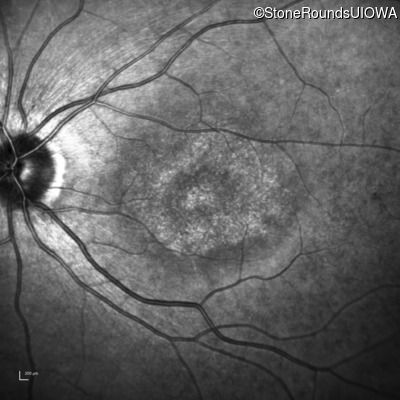

AR Stargardt Disease (IIA)

AR Stargardt Disease (IIA)

| AR Stargardt Disease | ABCA4 | Leu541Pro CTA>CCA, Ala1038Val GCC>GTC | Gln1003Stop CAG>TAG | AR |